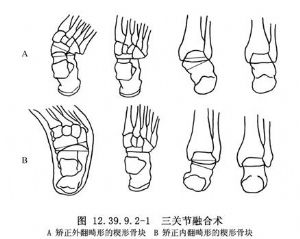

在马蹄外翻足中,内侧纵弓塌陷,距骨头增大并跖屈,同时前足外展。手术方法为抬起距骨头,将载距突内移至距骨头颈的下方以恢复内侧纵弓。切除一块包括一部分距骨头颈在内的基底朝内侧的楔形块(图12.39.9.2-1A)。后足外翻畸形矫正后,前足趋于旋后,这可通过做基底朝内侧的中跗关节楔形切除术来控制。为切除距舟关节,可能需要做内侧的附加切口。

在马蹄内翻足(图12.39.9.2-2)中,增大的距骨头位于足中轴线的外侧并阻碍背屈。做以外侧为基底的距下关节楔形切除术,同时结合中跗关节切除术,以此将距骨头置于足中轴线的稍内侧(图12.39.9.2-1B)。